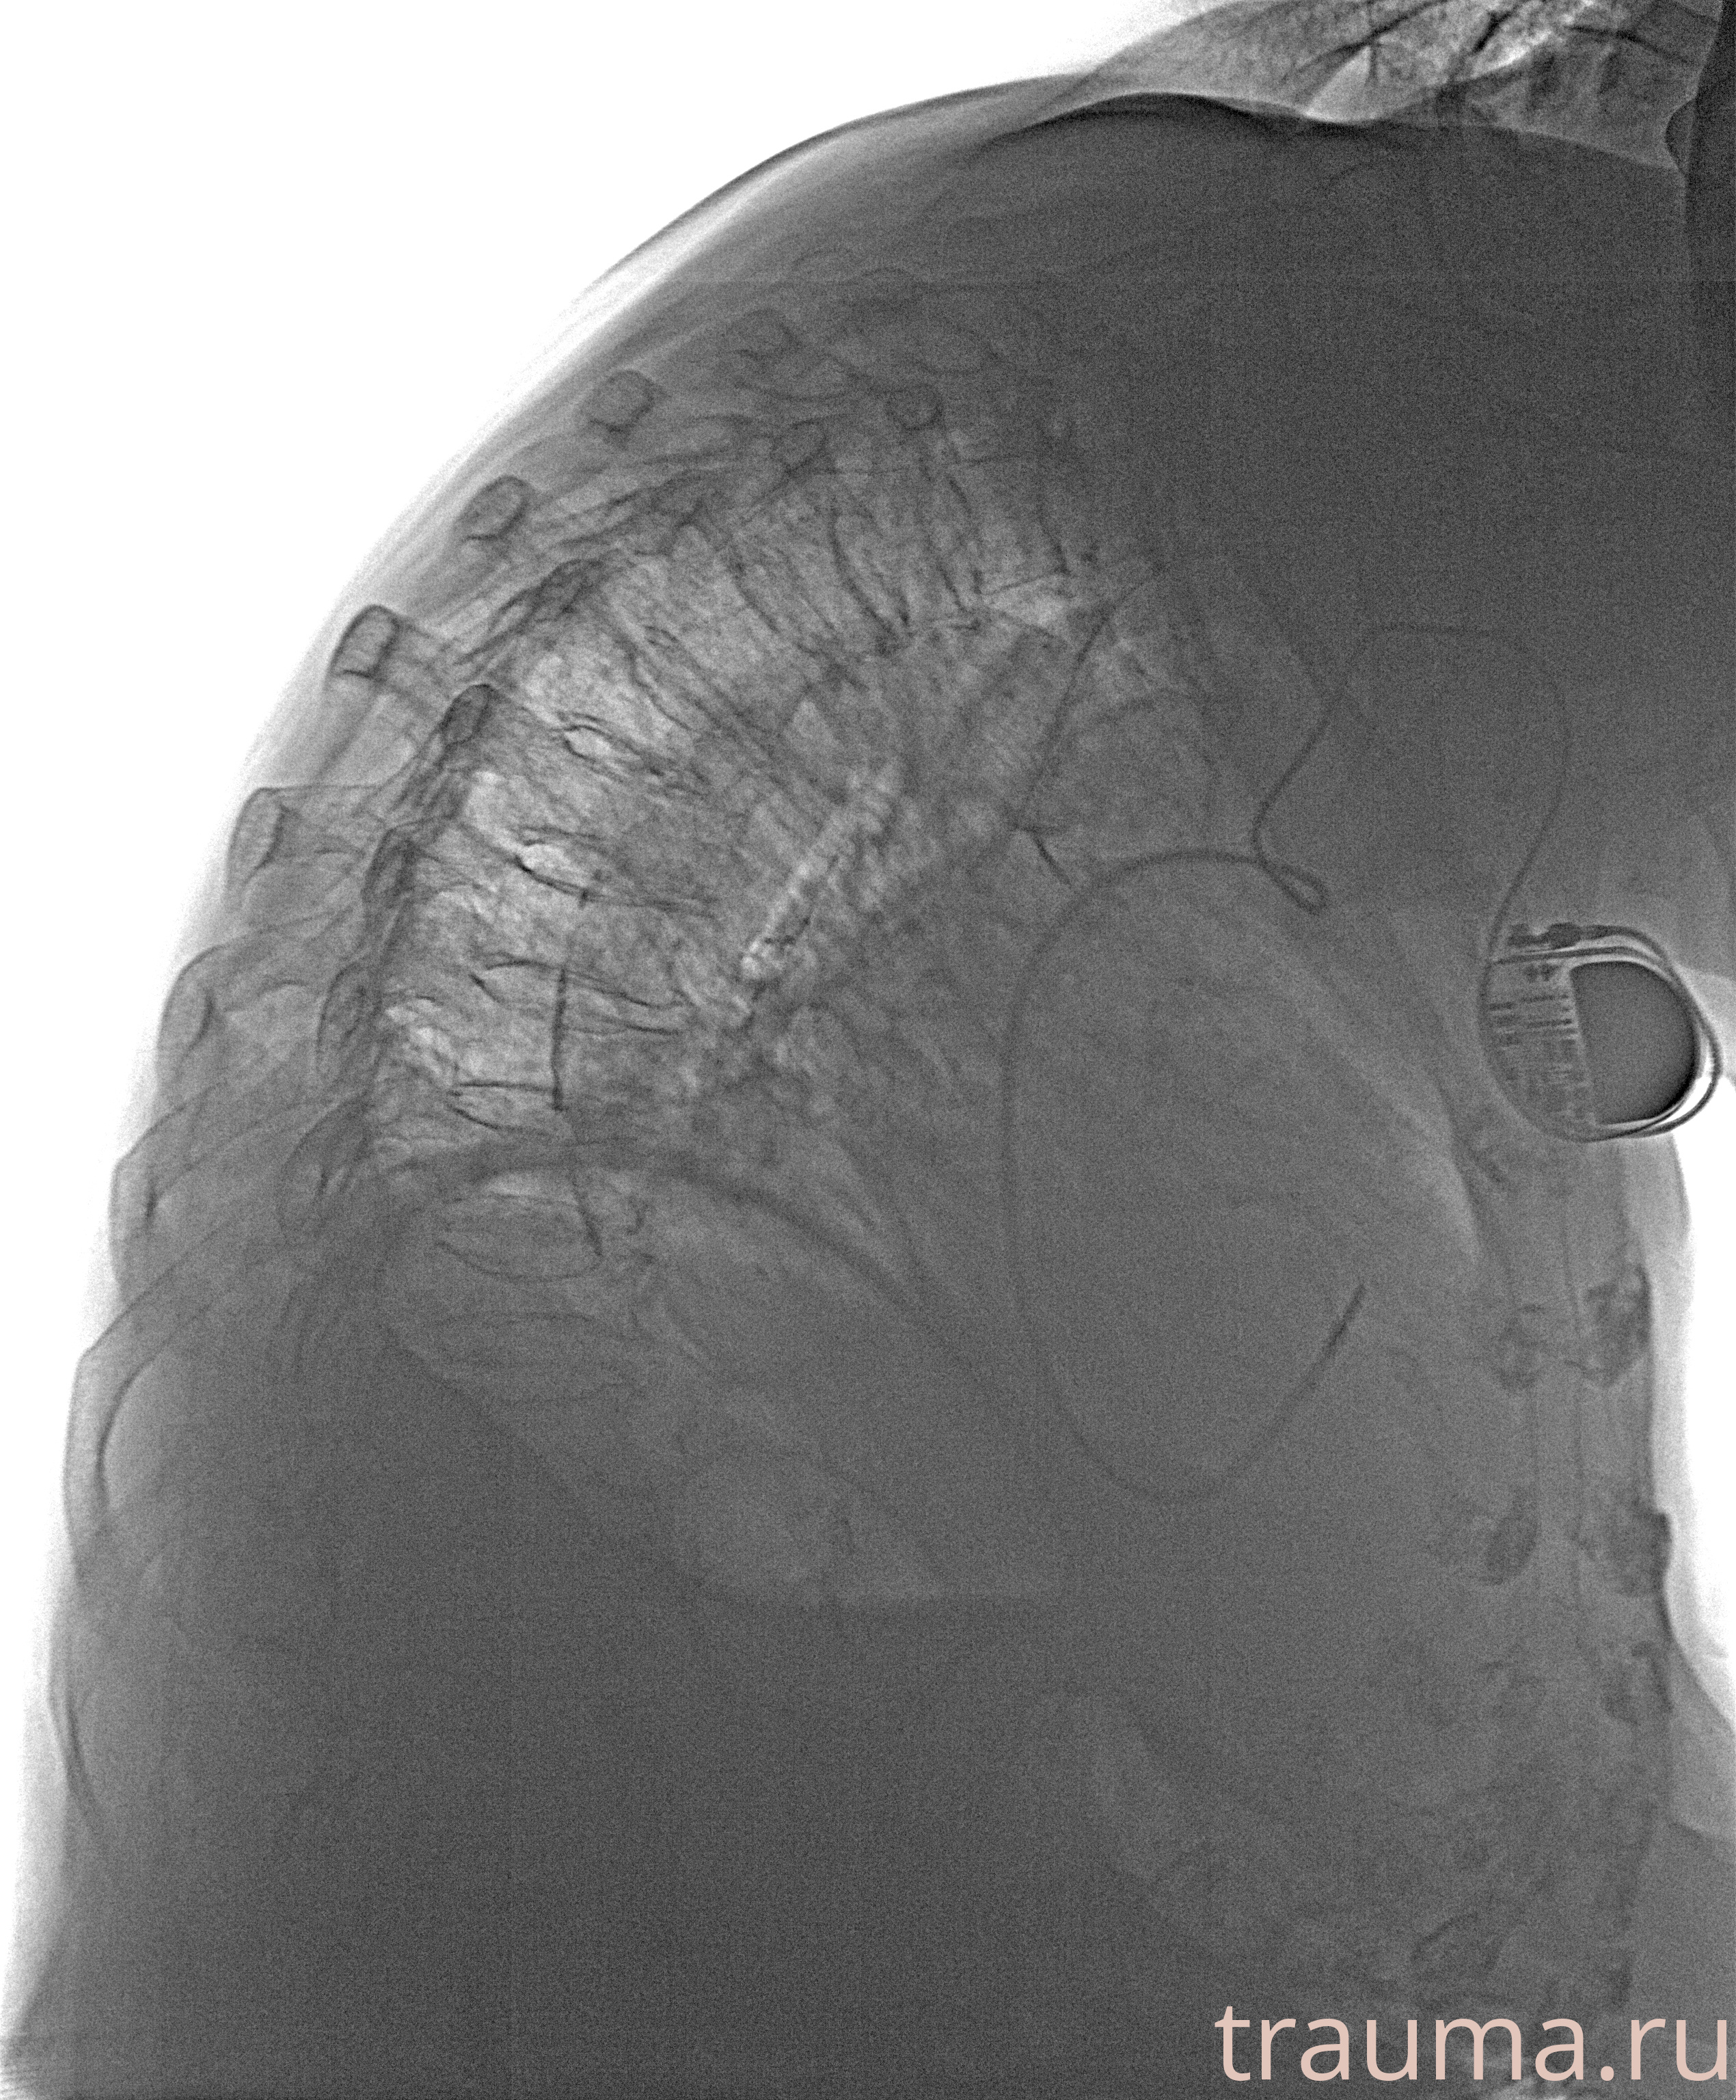

Рентгенограммы

Рентген на дому: по вашему адресу приезжает врач-рентгенолог, травматолог-ортопед с мобильным рентгеновским аппаратом, проводит диагностику травмы или заболевания, делает необходимые рентгенограммы, дает рекомендации по дальнейшему лечению. Получить качественные снимки в домашних условиях возможно благодаря уникальной методике, разработанной МосРентген Центром для института  Склифосовского